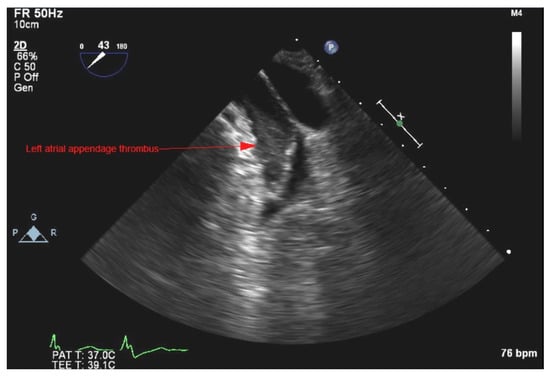

- Manning, W.J.; Weintraub, R.M.; Waksmonski, C.A.; Haering, J.M.; Rooney, P.S.; Maslow, A.D.; Johnson, R.G.; Douglas, P.S. Accuracy of transesophageal echocardiography for identifying left atrial thrombi. A prospective, intraoperative study. Ann. Intern. Med. 1995, 123, 817–822. [Google Scholar] [CrossRef] [PubMed]

- Durmaz, E.; Karpuz, M.H.; Bilgehan, K.; Ikitimur, B.; Ozmen, E.; Ebren, C.; Polat, F.; Koca, D.; Tokdil, K.O.; Kandemirli, S.G.; et al. Left atrial thrombus in patients with atrial fibrillation and under oral anticoagulant therapy; 3-D transesophageal echocardiographic study. Int. J. Cardiovasc. Imaging 2020, 36, 1097–1103. [Google Scholar] [CrossRef] [PubMed]

- Hubbard, E.; Wise, E.; Hubbard, B.; Girard, S.; Kong, B.; Moudgal, V. Tucked away: An infected thrombus. Am. J. Med. 2016, 129, 576–579. [Google Scholar] [CrossRef] [Green Version]